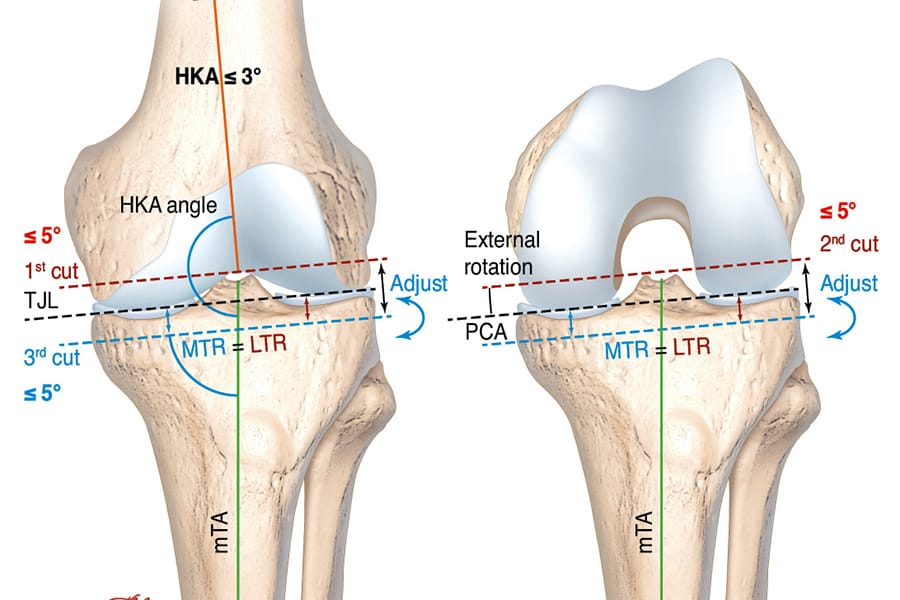

The clinical contributions in this issue address personalized alignment in TKA and examine why individualized TKA facilitates the restoration of native alignment, alongside current concepts and a glimpse into the future of partial knee replacement. A new perspective in cementless total knee arthroplasty broadens the implant discussion, while individualised therapy of femoral neck fractures — the Wiesbaden concept extends the scope to proximal femoral pathology.